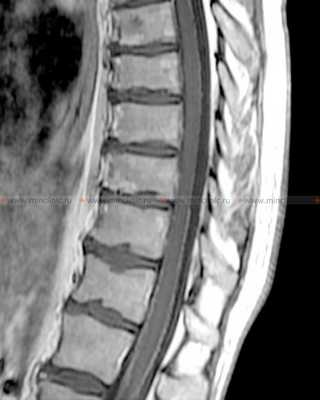

Компрессия ствола спинномозгового нерва С7 остеофитами. Сдавление нервов (стрелки) при заднелатеральном пролапсе двух нижних межпозвонковых дисков. МРТ, сагиттальная проекция.

Определяется пролапс диска L5/S1 с компрессией cauda equina (стрелка).